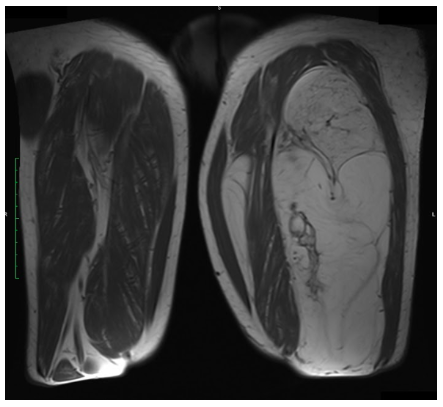

Radiographic imaging is used to help form a diagnosis. These include X-Ray, MRI, CT and Bone Scans

An example of MRI is shown.